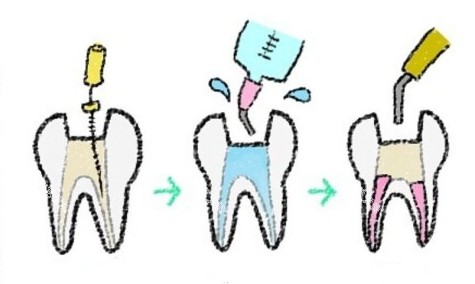

| 根管治疗 | 680起 |